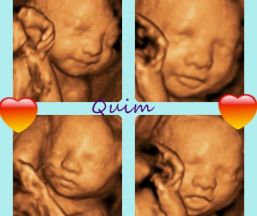

Realizamos ecografias4d prenatales emocionales a domicilio en la zona Barcelona y Girona y también en el centro médico Illadesalut en Sils(Girona).Realizamos ecografias 4d a partir de la semana 15/16 de embarazo para dar el sexo del bebé, escuchar su corazón, saber el peso, y conocerlo por primera vez.Si ya se conoce el sexo y sólo se va a realizar una ecografia4d las mejores semanas son entre la 25-30 pudiendo ver ya muy bien su c... seguir leyendo